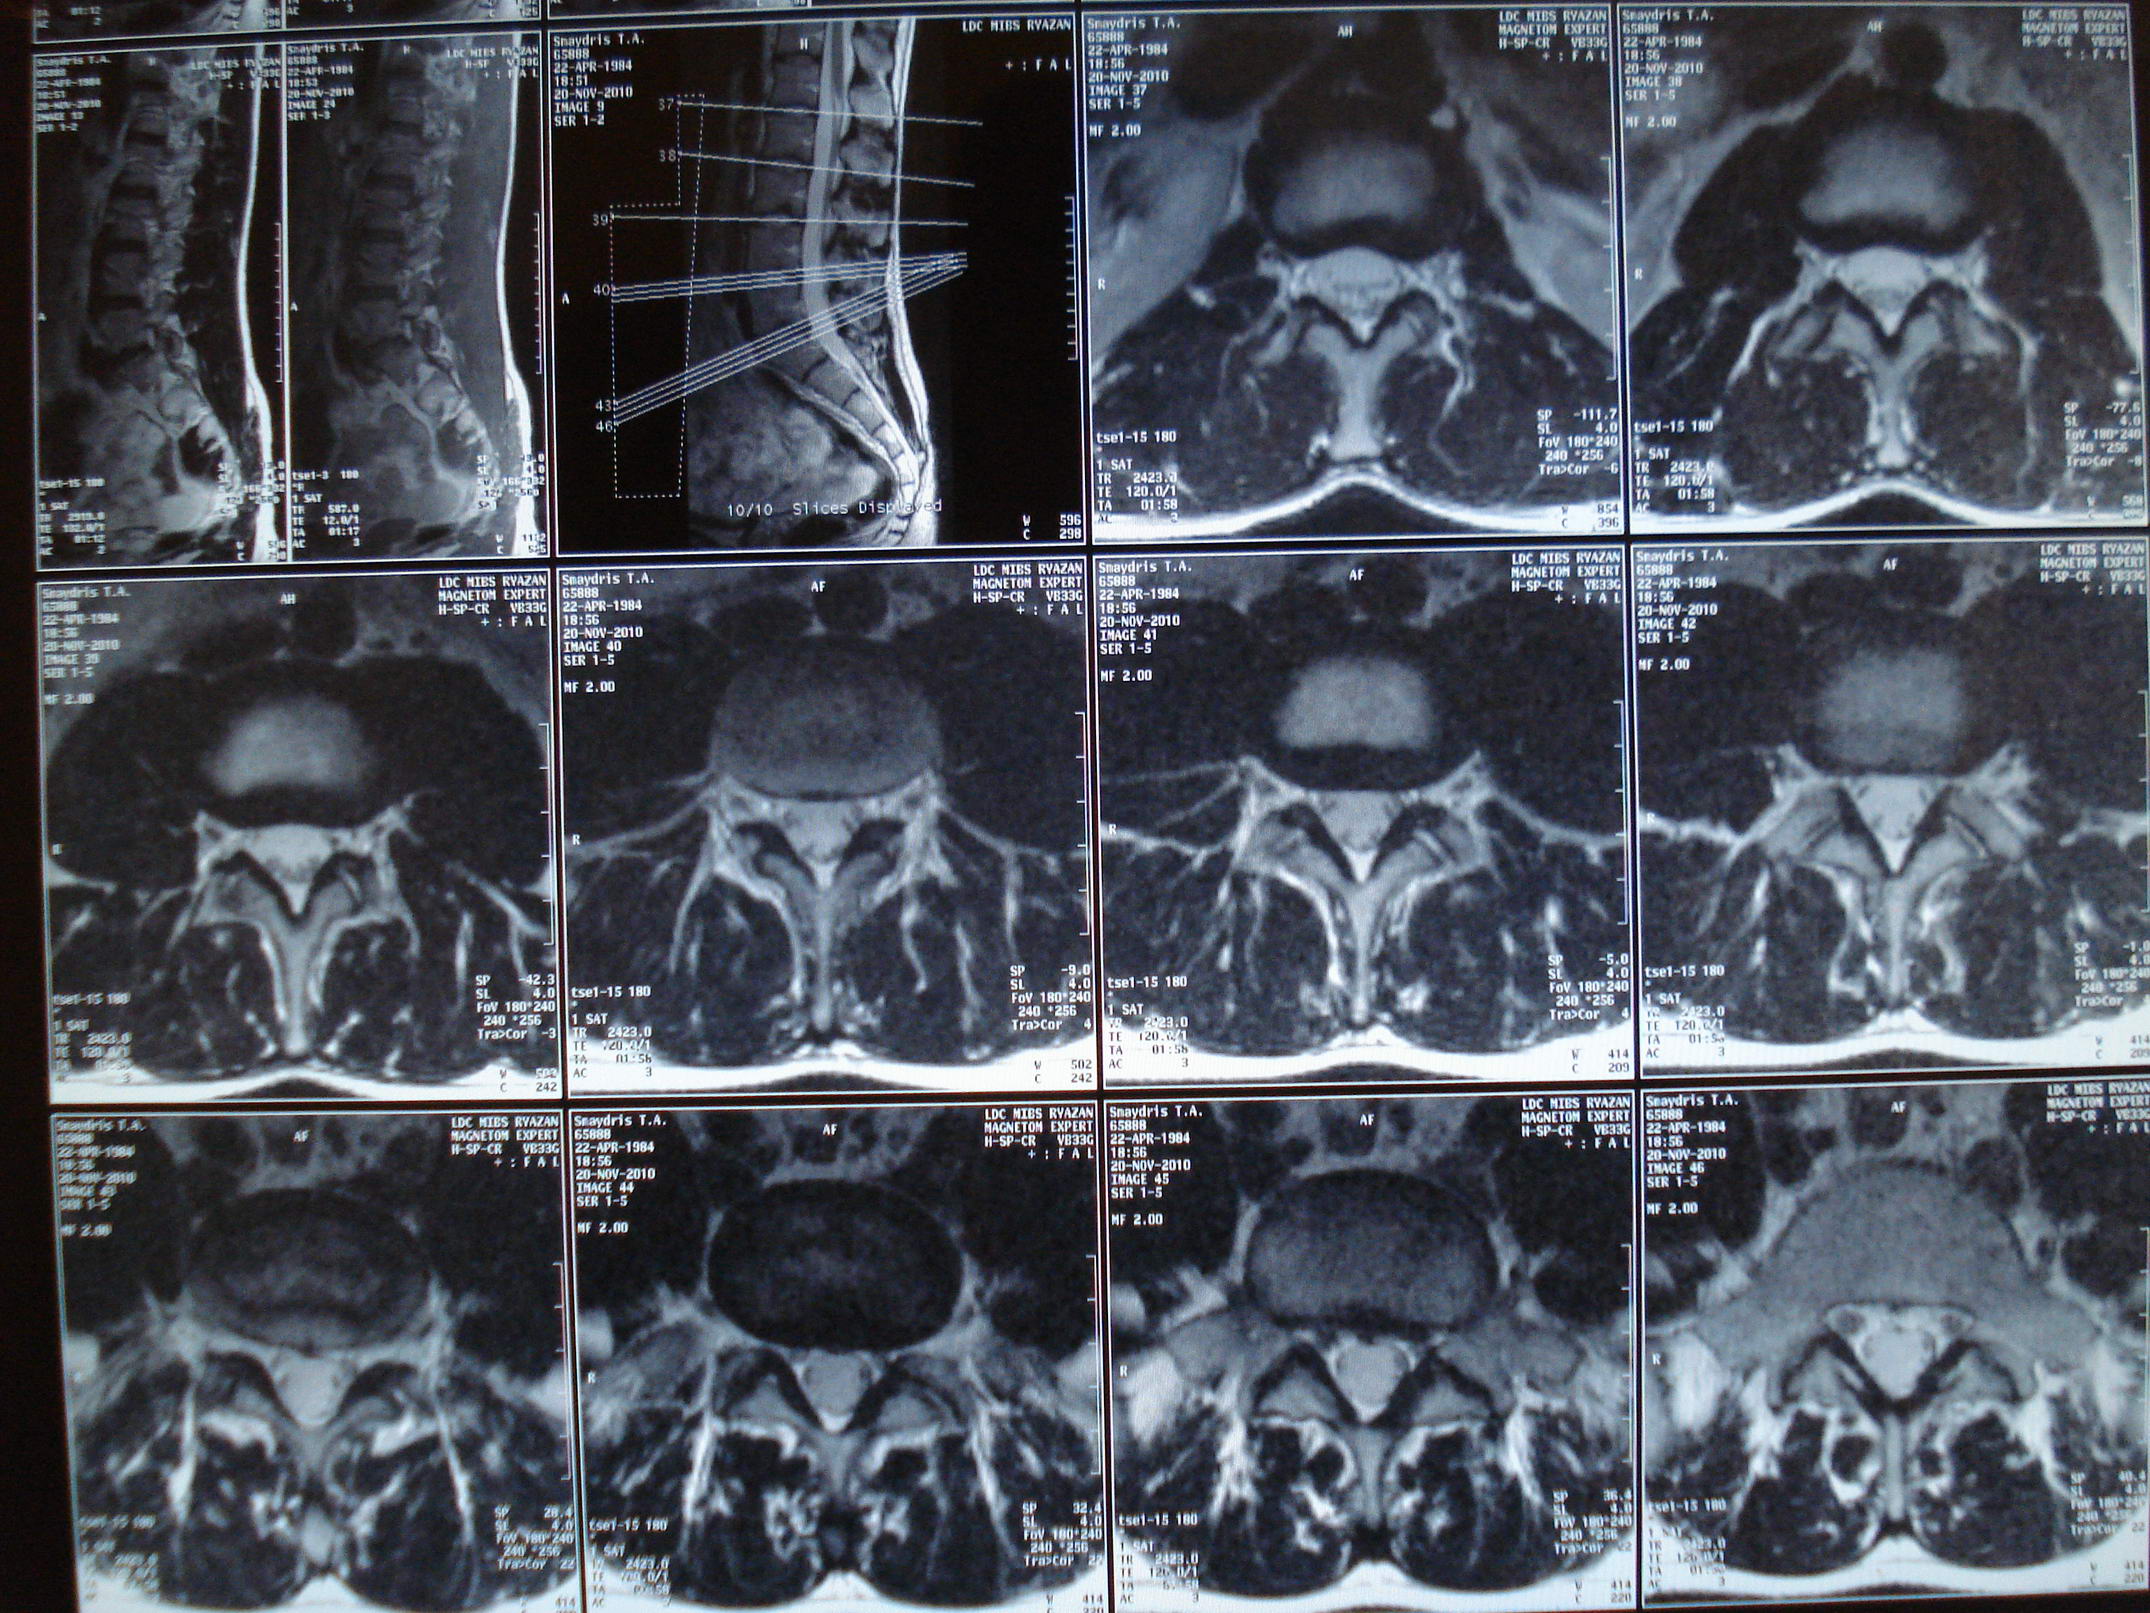

Введение Современная медицинская диагностика постоянно эволюционирует, открывая новые горизонты в понимании человеческого организма. В этом контексте одной из наиболее значимых и передовых технологий является магнитно-резонансная томография (МРТ). Эта…